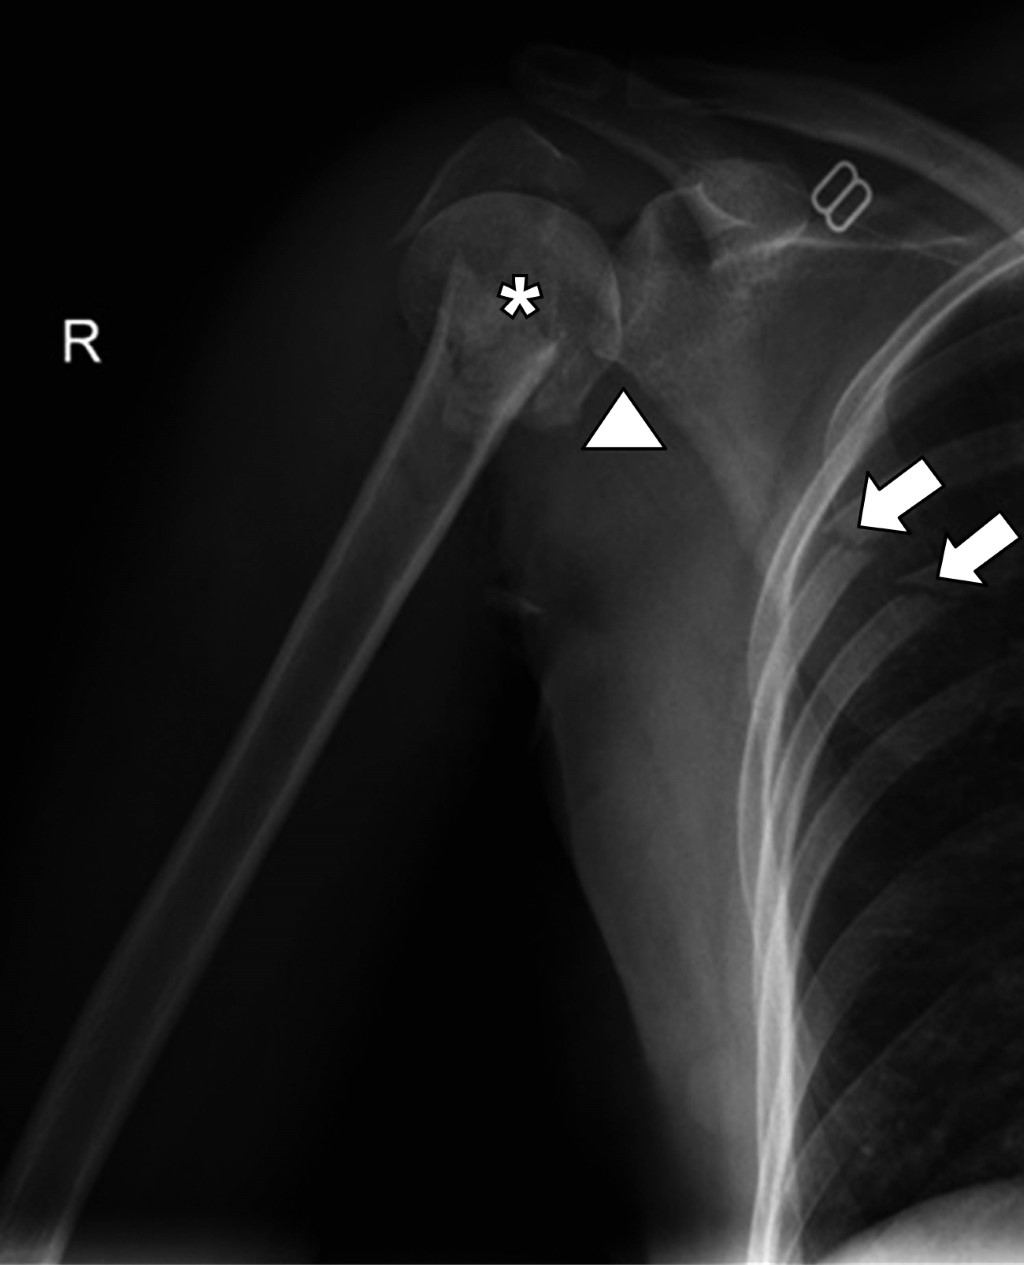

Multifragmentary proximal humerus fracture, the importance of MRI assessment

Proximal humerus fractures represent 45 to 50% of humeral fractures, and the main risk factors are falls, age, osteoporosis, and high-impact sports. The initial diagnostic method for assessing bone structures is radiography, which can be complemented with a tomographic study to assess the fracture line and associated characteristics. In multi-fragmentary fractures with complex lines, the trend of using magnetic resonance imaging is on the rise, as it allows the evaluation of myotendinous and ligamentous structures, which are limitedly evaluated in studies based on ionizing radiation.

Figure 4